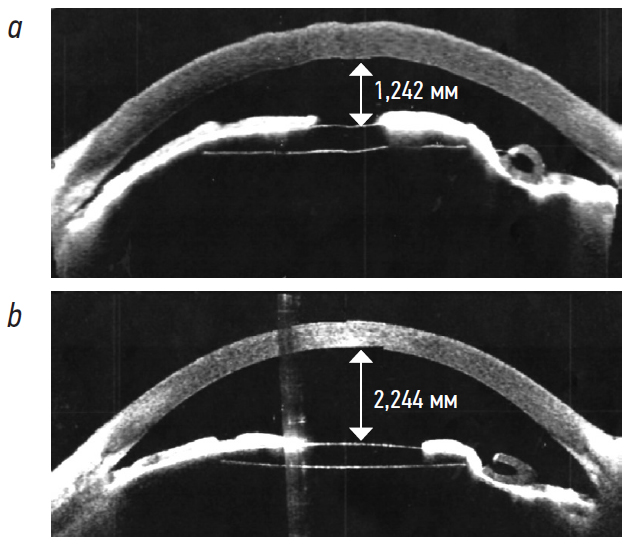

In the early postoperative period, biomicroscopy in patients in group 2 revealed anterior chamber shallowing associated with silicone oil in the vitreous cavity (Table 2). During postoperative follow-up, adherence to the recommended “correct” position of patients in bed (the prone position for patients with light silicone oil tamponade, and the supine position for patients with heavy silicone oil tamponade) in combination with local glucocorticoid therapy enhanced the treatment effect in this group. This complication resolved in all cases within 2–5 days (Fig. 4).

Fig. 4. Optical coherence tomography of the anterior segment of the right eye 1 day after surgery (a) and 3 days after surgery (b)

Рис. 4. Оптическая когерентная томография переднего отрезка правого глаза в первые сутки после операции (a) и третьи сутки после операции (b)

Selection of the Ahmed valve implantation area is often limited by conjunctival scarring after prior repeated vitreoretinal procedures. Another issue is migration of silicone oil under the conjunctiva as it contributes to chronic inflammation and fibrosis, which require prolonged administration of glucocorticoids and non-steroidal anti-inflammatory drugs and also promote the formation of a connective tissue capsule around the drainage device body [10, 24]. Complications of drainage device implantation after VRS with silicone oil tamponade are common and vary from mild, such as postoperative hypertension, hypotony (up to 50% of patients [23]), hyphema, or inflammation, to more serious, e.g. choroidal detachment, keratopathy caused by corneal contact with the device tube, and diplopia caused by implantation in the inferior temporal quadrant (the last two complications require re-implantation more often). In our study, complications in the early postoperative period included hyphema (11%–13% of cases) and choroidal detachment (1 case), with anterior chamber shallowing being the most common (40% of cases) in patients with silicone oil tamponade without concomitant ciliary body detachment. We find anterior chamber shallowing a pathognomonic complication in patients with silicone oil tamponade. After implantation, the valve immediately starts to drain aqueous. This may lead to silicone oil (with higher density than aqueous) moving the lens-iris diaphragm forward (more often with zonular defects and iris atrophic changes), which takes time to restore the anterior chamber.